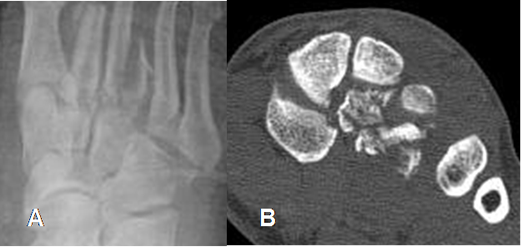

Fig 55 A. Fractura de metatarsianos.

A: Rx AP. Pérdida de la nitidez en las 2º y 3º articulaciones tarsometatarsianas, por fracturas.

B: TAC reconstrucción coronal. Fracturas conminutas en la cuña media y lateral, las cuales están desplazadas posteriormente.